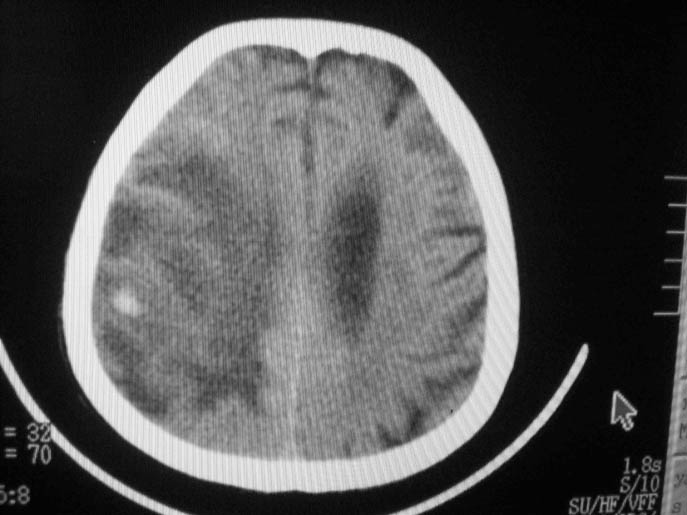

以下是引用卜一在2009-9-7 16:23:00的发言:[br]支持:胶质瘤伴出血!

以下是引用随光逐影在2009-9-8 7:40:00的发言:[br]考虑脑转移瘤或胶质瘤并肿瘤卒中;建议行ct增强扫描检查。

以下是引用熊熊在2009-9-7 18:31:00的发言:[br]胶质瘤伴出血[br]建议增强